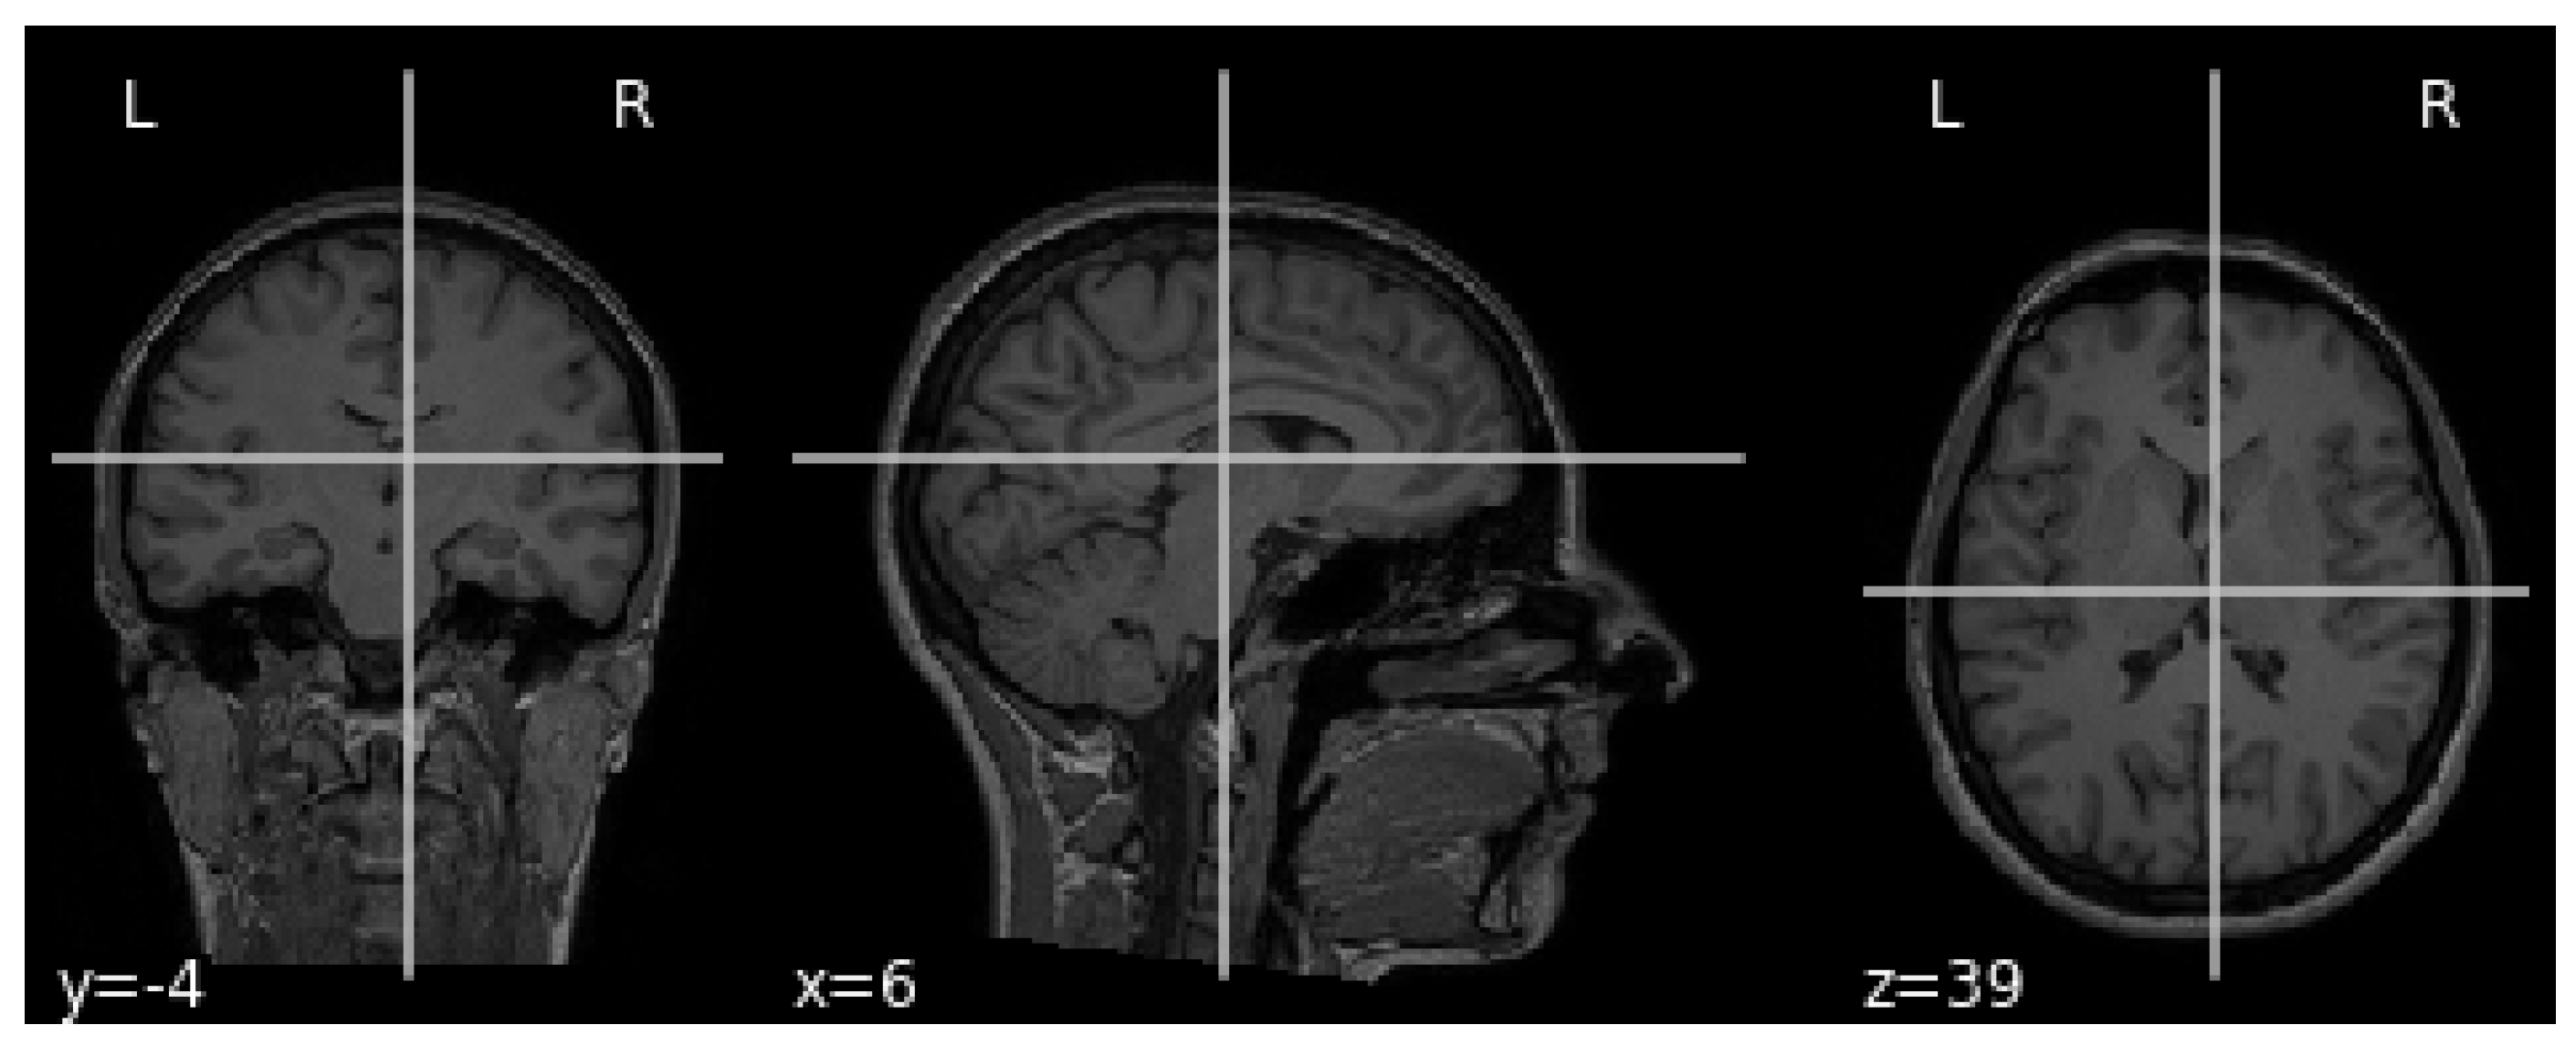

The MRI requires the setup of specific parameters, including radio-frequency pulse and gradient. T1 and T2 sequences are usually used in practice, with both providing specific information about the observed tissue. This research uses the T1 sequence. To reduce the amount of images required for the healthy brain, six sections were chosen from MRI images. A healthy brain sample is shown in Figure 3.

To help distinguish the tumor tissue and more precisely determine the tumor borders, the patients are typically injected with a contrast solution (Gadolinium). These images can be utilized in the classification of the tumor grade. Figure 4 shows axial MRIs with Gadolinium infusion of three grades of glioma brain tumors. Finally, Figure 5 shows three brain tumor cases from the second dataset utilized in this research [81]. As mentioned, all employed images were normalized to the [ 0 , 1 ] interval, and their dimension was set to 128 × 128 pixels.